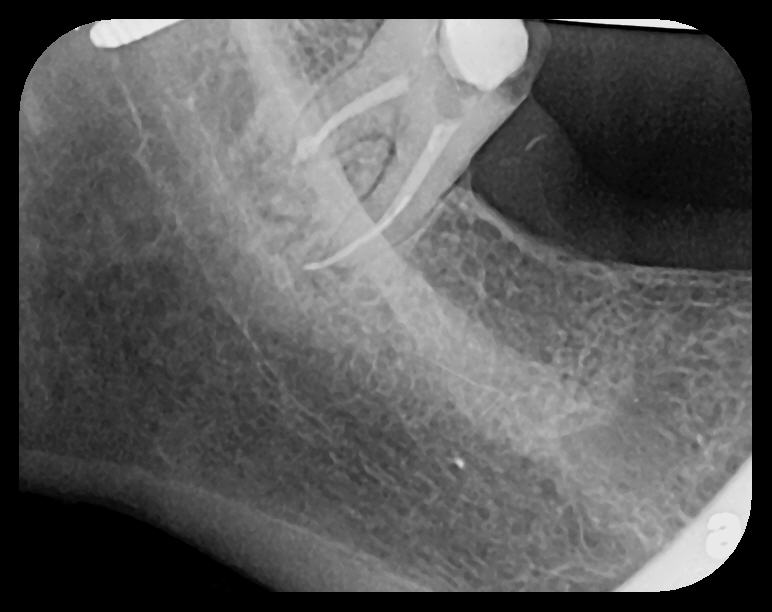

Fig 2. Left: PSP vertical PA radiograph of

maxillary bicuspid area demonstrating full root structure, several millimeters of bony anatomy beyond apices and maxillary sinus. Tooth No. 4 may be

traumatized as periodontal ligament is widened. Right: PSP horizontal PA radiograph of maxillary bicuspid area. Tooth No. 12 shows widened apical

periodontal ligament presumably caused by deep restorative filling. Some loss of supporting bone is evident interproximally, especially pronounced

between tooth Nos. 14 and 15.

Figure 2

Fig 3. Two PSP PA radiographs of mandibular teeth showing: left, the initial view

of molar area and suspected pathology surrounding impacted tooth No. 32; center,

subsequently exposed PA radiograph, placed more distally, demonstrates extent

of large cyst as well as entire tooth and root No. 32. Proper alert as to presence

of suspected cyst and appropriate referral for 3D CBCT study and surgical

enucleation was given to the patient. Right: Same radiograph as on the left, but

with lighter superimposed outline of the area that would be visible using an HW

sensor rather than a PSP sensor. The small area of pathology is likely obscured

because it is visually overlaid by the root of tooth No. 31. Neglect of this significant

pathology may have resulted.

Figure 3